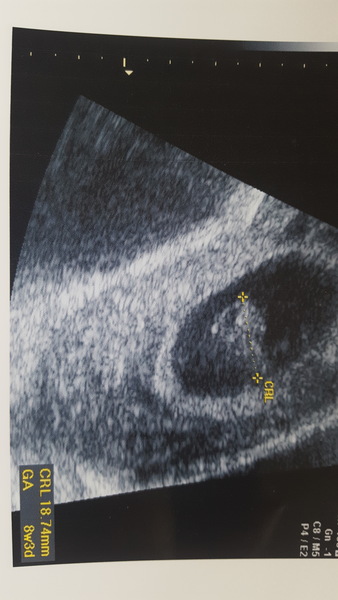

Here we go! Eeeek! Saw the little heart going too, absolutely magical! Nausea is easing off ever so slightly, find it helps slightly if I have rice crackers asap after getting up to just have something in my tummy. Struggling to get up much appetite much unlike me and lots of food makes me gag. Most days there's just one specific thing I might be able to manage for tea and the meal plan goes out the window! On Tuesday I came home from a long stressful day at work and just cried because I desperately wanted a pesto pizza. I don't even really like pesto that much! Only managing small portions of everything bit hopefully it's getting better! Good luck with your trip hope all okay. Xxx

Aw so cute! Amazing the size difference in just a week! I'm the same, all I've managed today is a chocolate milkshake and prawn crackers, the most random flavour combinations ever!!

Nice seeing your photos kittykat and lamchanging :-) they look bigger that I would've expected!